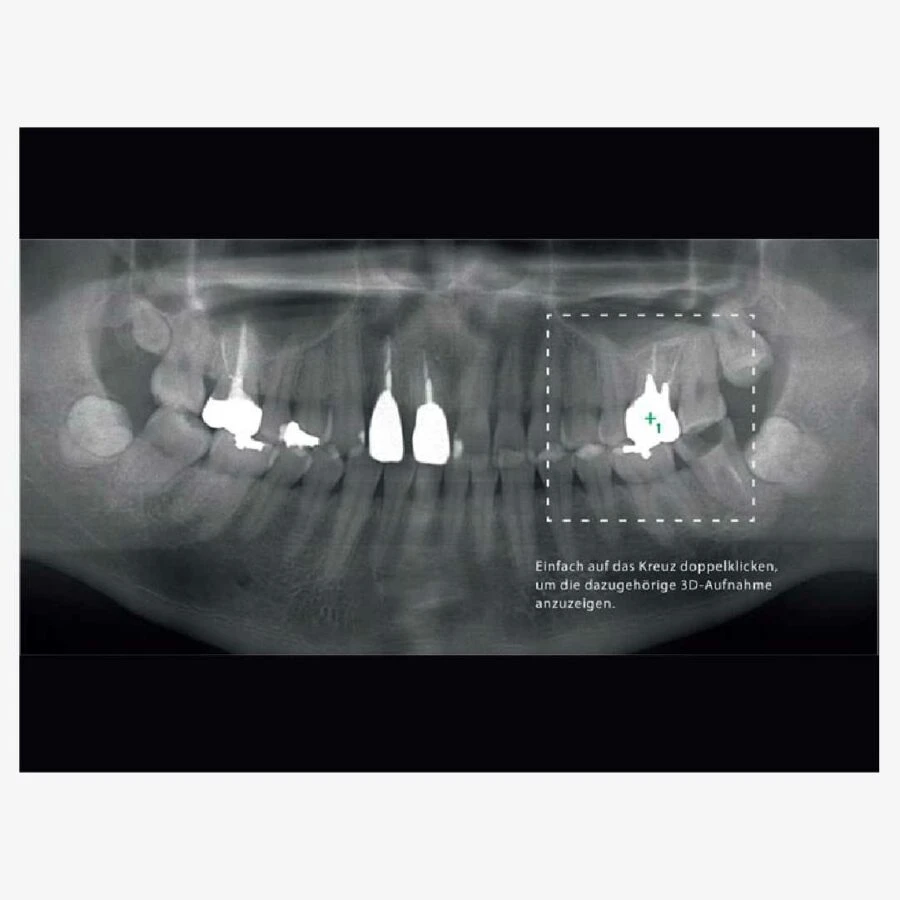

Hình ảnh toàn cảnh với đặc tính dò tìm

Dò tìm theo 2 chiều

Xác nhận vị trí cấy ghép với hình ảnh mô phỏng 3D

Kết nối đến phần mềm mô phỏng cấy ghép

– Có chức năng chụp ảnh toàn cảnh theo từng phần: không cần chụp ảnh toàn hàm đầy đủ ta có thể chụp chế độ từ 1 đến 5 phần của vùng ảnh toàn cảnh cũng như xoang hàm trên. Có thể bỏ các vùng không cần quan tâm để giảm liều tia bức xạ